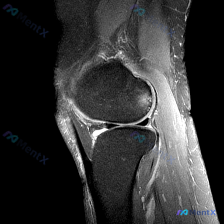

初始怀疑软骨异常,MRI却找出了关键问题?这个膝关节病例很有启发

最近看到一份膝关节MRI读片需求,初始焦点指向「软骨异常」,整理了完整的分析思路分享给大家。

这是一张膝关节MRI矢状位脂肪抑制序列(FS-T2/PD-FS)图像,信噪比、对比度良好,无明显运动伪影,定位为:右侧是前(髌骨侧),左侧是后(腘窝侧)。该序列液体呈高信号,骨髓脂肪信号被抑制,方便区分水肿和正常组织。

- 骨骼骨髓:股骨远端、胫骨近端骨髓信号正常,无弥漫性水肿,形态完整

- 关节软骨:股骨滑车、胫骨平台软骨显示清晰,未见明确剥脱或全层缺损

- 半月板:本次层面未见延伸至关节面的异常高信号(无III级撕裂征象)

- 韧带:后交叉韧带走行自然、信号均匀、连续性好;前交叉韧带本层面未完全显示

- 髌周结构:髌骨后方关节面平整,间隙无狭窄,Hoffa脂肪垫信号均匀

- 关节腔滑膜:髌上囊及关节间隙可见少量积液,呈高信号

核心阳性发现

- 髌上囊区域存在少量关节积液

- 腘窝区域可见边界清晰、信号均匀的囊性高信号病变,位于关节囊后方,符合腘窝囊肿(Baker's cyst)的典型影像学表现

- 髌骨前方皮下软组织层次清晰,无异常